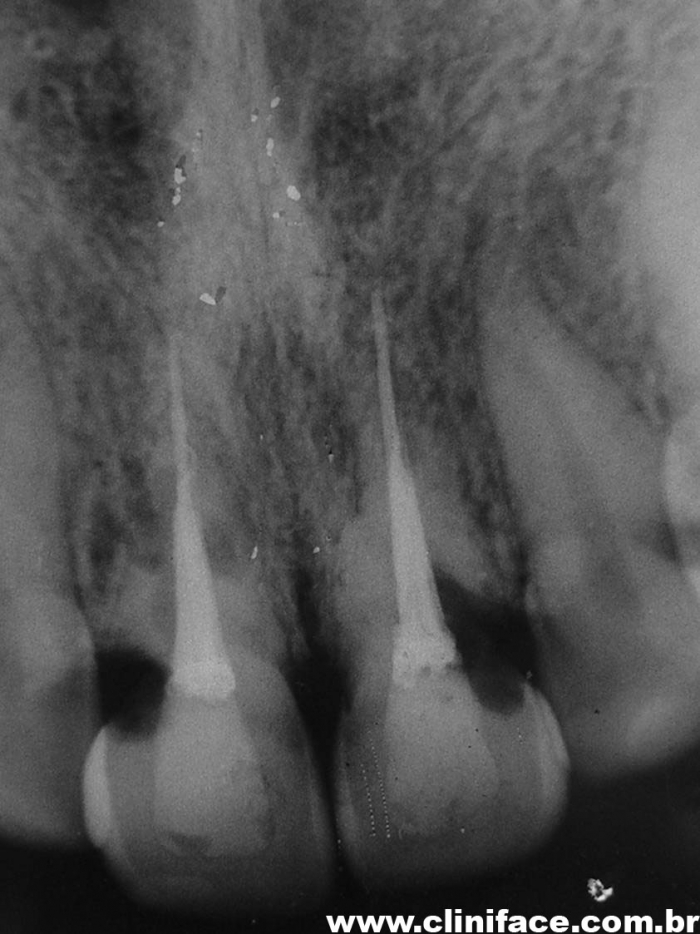

Rx após extração e implantes imediatos